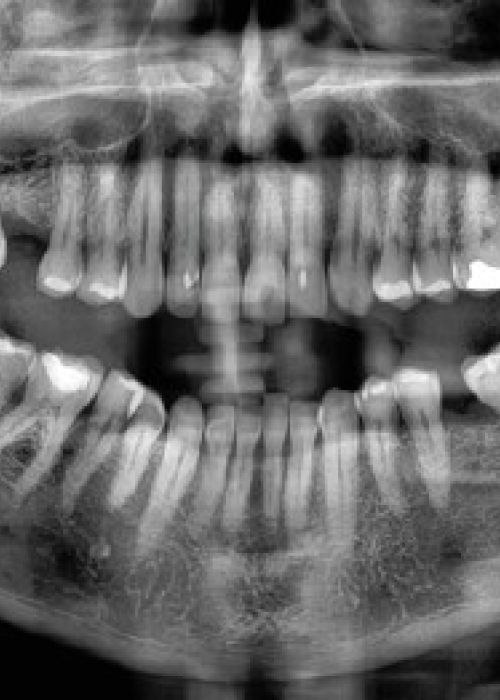

Síndrome de Papillon-Lefèvre